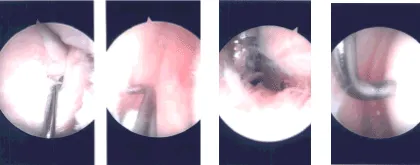

Intraoperative Arthroscopy Images

A left lateral entry portal was made through the and arthroscope was inserted. Medial entry portal was made with the use of spinal needle. Examination of the medial tibiofemoral compartment showed grade 4 osteoarthritic changes of the medial tibial plateau and grade 1 to grade 2 osteoarthritic changes of the medial femoral condyle.

It showed tearing of the medial meniscus in the region of the junction of the body and the posterior horn going into the posterior horn. Debridement of the medial meniscus was done with the use of shaver and biters. Debridement of the cartilage was also done with the use of shaver.

Abrasion chondroplasty of the tibial surface. Examination of the intercondylar notch showed degenerative ACL but not tear. Examination of the lateral tibiofemoral compartment showed no arthritis and no tear.

Examination of the patellofemoral compartment showed grade 2 to grade 3 osteoarthritic changes of the trochlea as well as patella. Debridement of the trochlea and patella was performed with the use of a shaver.

There was extensive synovitis in the suprapatellar region which was debrided with the use of shaver. Histopathology was sent for all the shavings. Final picture was taken and saved.